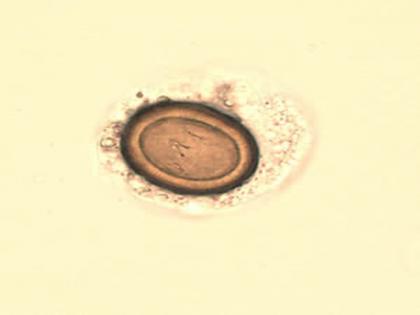

पत्ता कोबीमध्ये एका प्रकारच्या अळ्या असतात. त्यांना टेपवर्म म्हणतात. ही टेमवर्म पोटात गेल्यास रक्तप्रवाहासोबतच शरीराच्या इतर भागांवर सुद्धा परिणाम करत असते. तर काही प्रकारच्या अळ्या या डोळ्यांना दिसणार सुद्धा नाही अशा लहान आकाराच्या असतात. पण जर यापासून बचाव करायचा असल्याल कोबीची भाजी घरी तयार करण्याआधी चिरून उकळून घ्या. उकळल्यामुळे त्यातील शरीरासाठी अपायकारक ठरणारे घटक नष्ट होतील.

टेपवर्म पावसाच्या पाण्यामुळे किंवा अन्य काही कारणामुळे जमिनीत पोहोचतात. नंतर ते भाज्यांवर आल्याने त्या माध्यमातून शरीरासाठी घातक ठरतं असतात. टेपवर्ममुळे शरिराला जे ईन्फेक्शन होते त्याला टॅनिएसिस (taeniasis) असं म्हणतात. ज्यामुळे शरिराच्या आतल्या भागात जखमा होतात.